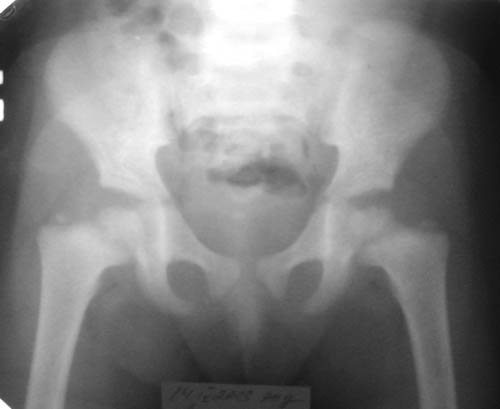

Девочка, 3 года 11 мес. Дз: Фосфатдиабет (витамин Д-резистентный рахит).

Жалобы на задержку роста. Общие анализы крови и мочи без особенностей.Биохимический анализ крови: билирубин 7,7, АЛТ 0,30, общий белок 73, креатин 0,061, щелочная фосфотаза 49%мл/г, K+ 4,4, Na+ 139, Ca++ 0,93, Ca общий 2,5.УЗИ органов брюшной полости: норма, печень увеличена, паренхима однородна, сосудистый рисунок сохранен. Рентгенологический возраст 2 года, хронологический возраст 4 года. Ранее рекомендована ЛФК, витамины, видеин.Рекомендации по лечению? Заранее благодарен! С уважением, А.В.Владзимирский Донецкий НИИ травматологии и ортопедии